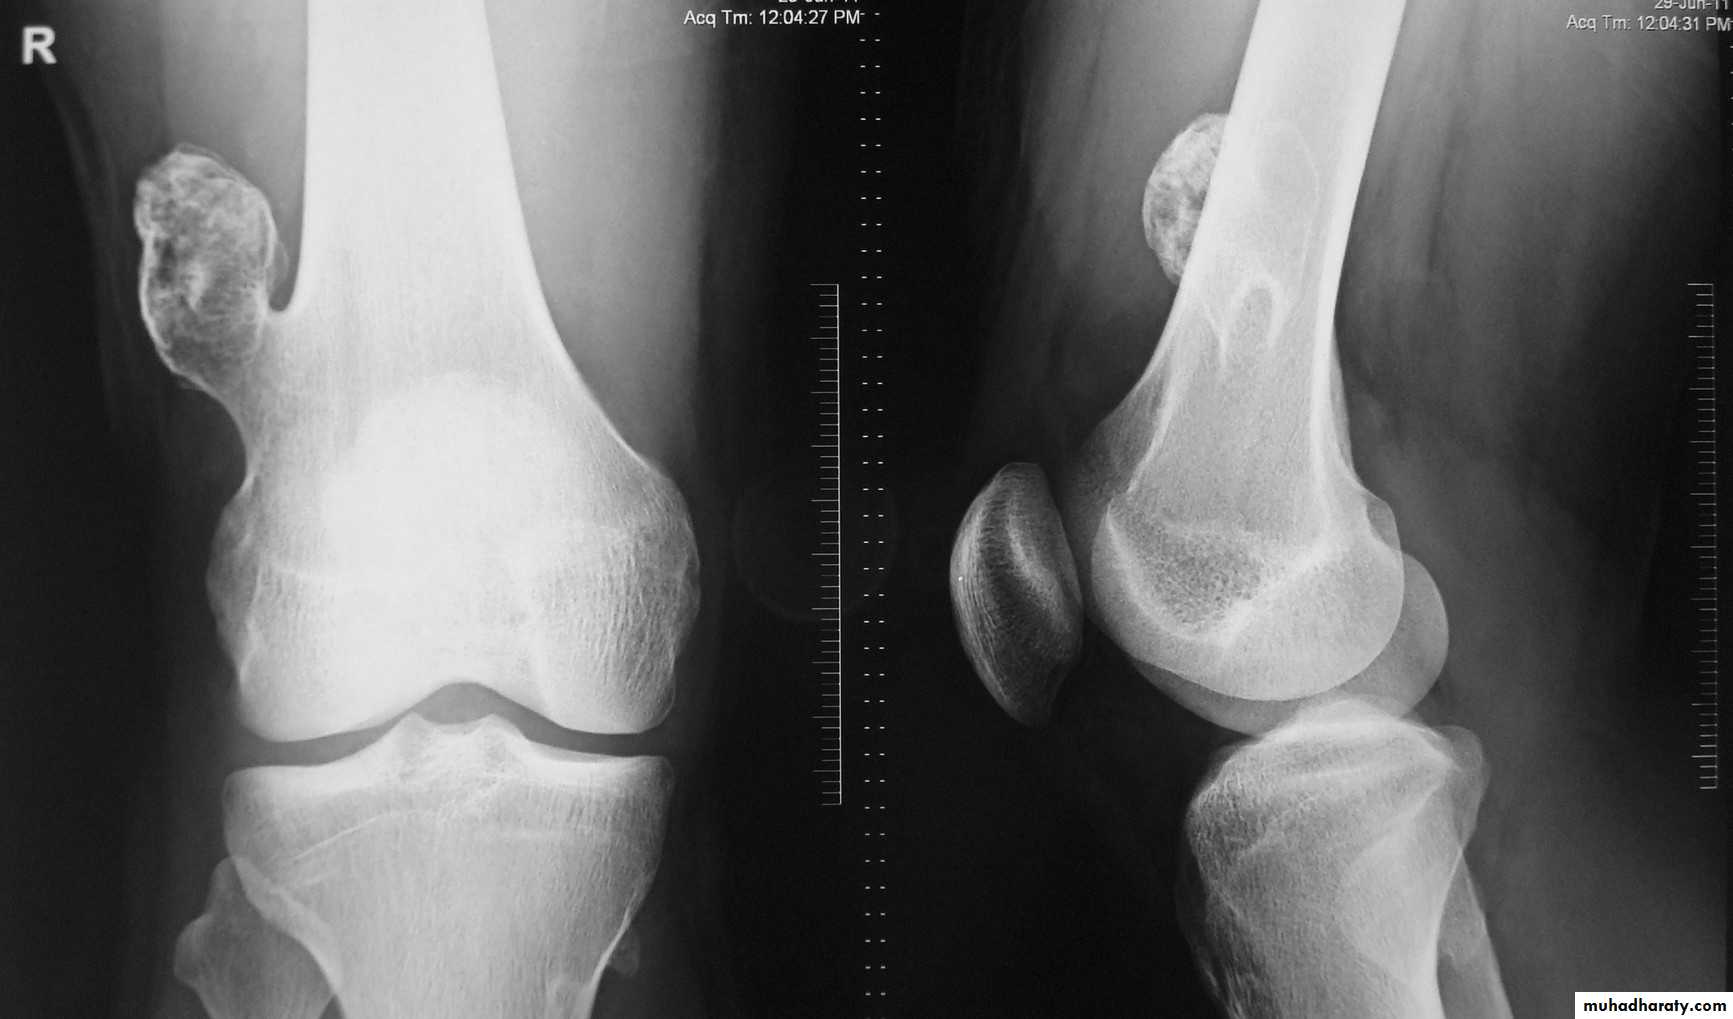

Tumor have slender pedicle directed from growth plate ,,, what it could be ???

Is the direction of pedicle toward joint or away ?????What is being have at upper aspect ???

What is their significance ???

Answer .Osteochondroma Most common benign bone lesion which have their own growth plate)

Pedunculated: slender pedicle directed away from growth plate .The thickness of the cartilage cap above the bony projection is very important

if the thickness > 1 cm of cartilaginous cap by CT, > 2 cm by MRI give high possibility of Malignant transformation

Also Dispersed calcifications in the cap